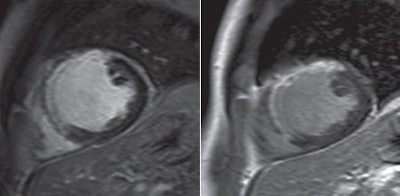

| MR images are of a 47-year-old man. Gadopentetate-enhanced image (left) shows large anterior transmural myocardial late enhancement, while corresponding gadobutrol-enhanced image (right) shows the same area, extension, and transmurality of infarct. Images courtesy of AJR. |

The significance of the study, according to the authors, is that late enhancement from single-dose gadobutrol for the first time was "not inferior" to results from double-dose gadopentetate dimeglumine. Their conclusion was supported by similar results in the pattern of contrast distribution, signal-to-noise ratio, and contrast-to-noise ratio.